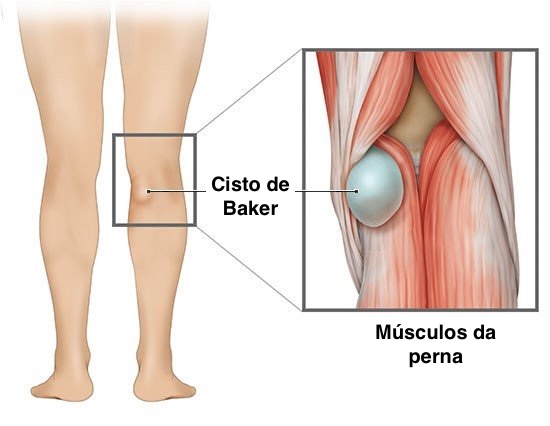

O cisto de Baker é um acúmulo de líquido sinovial na parte de trás do joelho, geralmente localizado entre o tendão do músculo semimembranoso e a cabeça medial do gastrocnêmio. Esse líquido vem da própria articulação do joelho e se acumula nessa região quando há aumento de pressão intra-articular ou inflamação persistente.

O joelho produz líquido sinovial para lubrificação e nutrição da articulação. Quando existe artrose, meniscopatia, sinovite ou outra alteração inflamatória, a produção de líquido pode aumentar. Parte desse líquido pode passar para a bursa gastrocnêmio-semimembranosa e ficar retido ali por um mecanismo semelhante a uma válvula de sentido único.